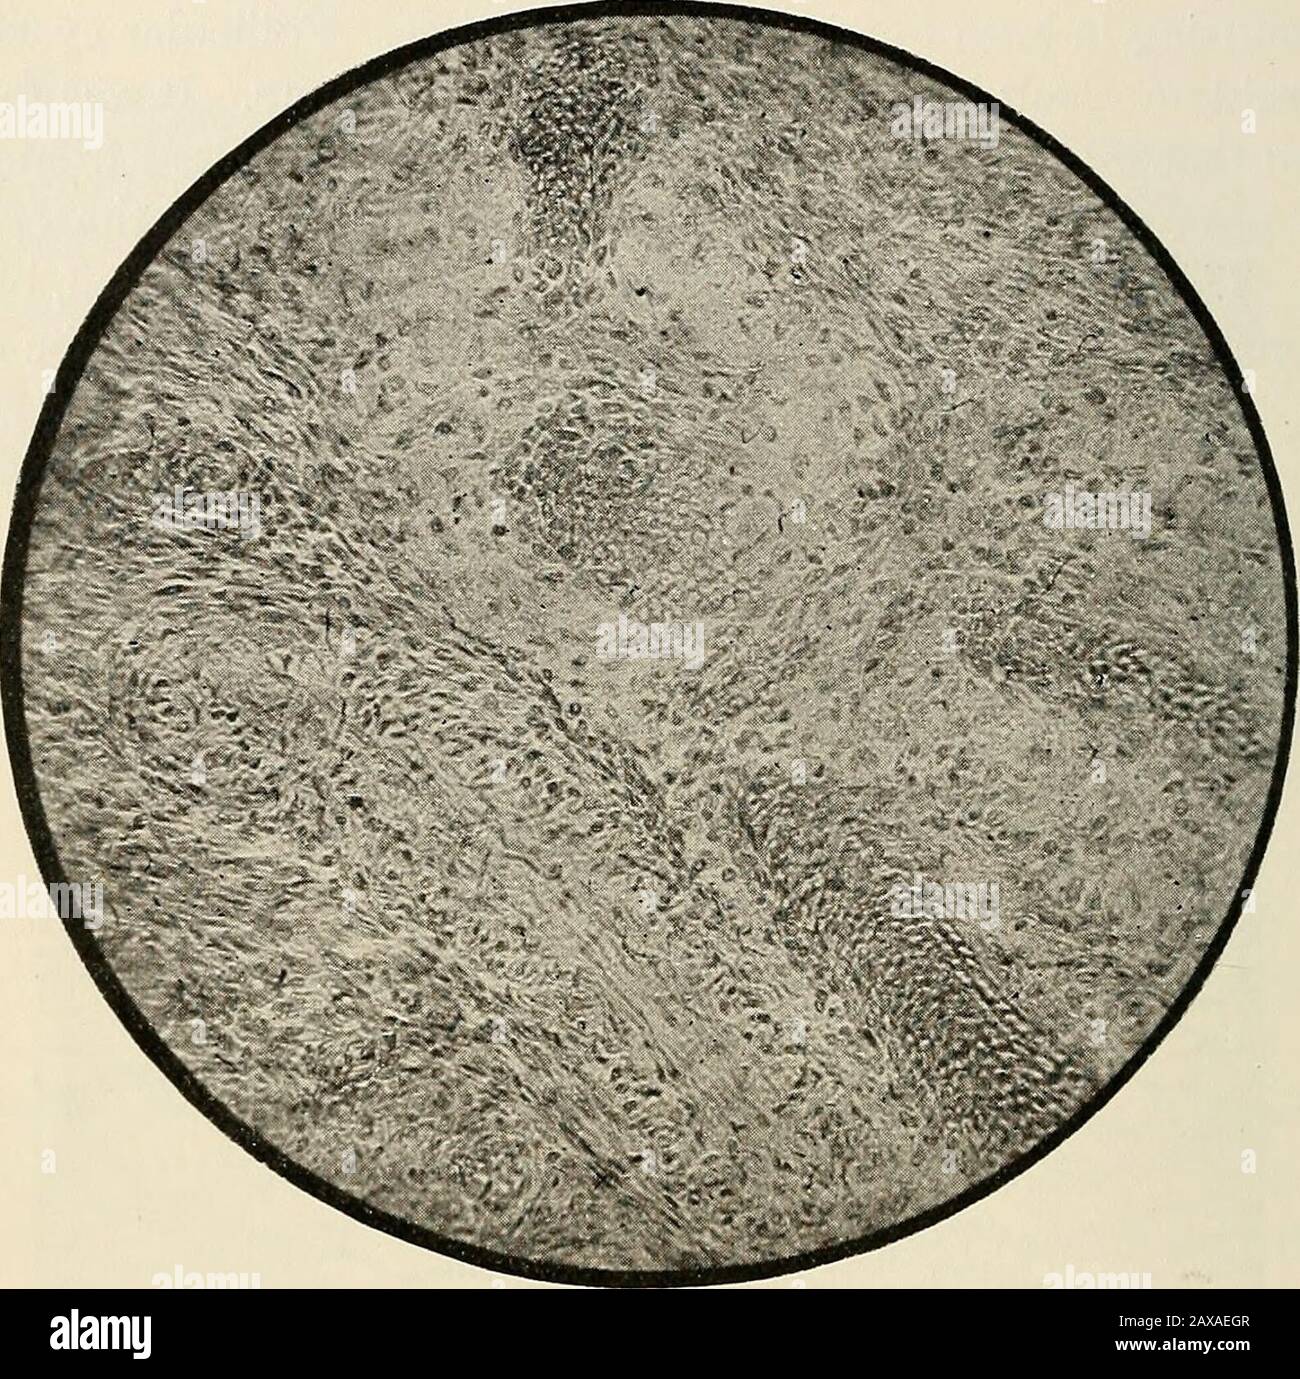

Myxomatos Stockfotos Und Bilder Kaufen Alamy